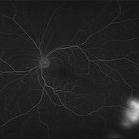

Proliferative Sickle Cell Retinopathy (Stage3) (10 files)

Proliferative Sickle Cell Retinopathy (Stage3) (10 files)

Sickle Cell Retinopathy (11 files)

Sickle Cell Retinopathy (11 files)

Sickle Cell Retinopathy SC (6 files)

Sickle Cell Retinopathy SC (6 files)